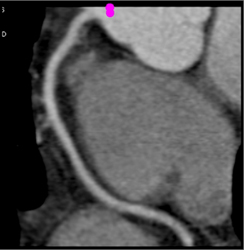

Plaque Without Stenosis in Circumflex Artery (CX)